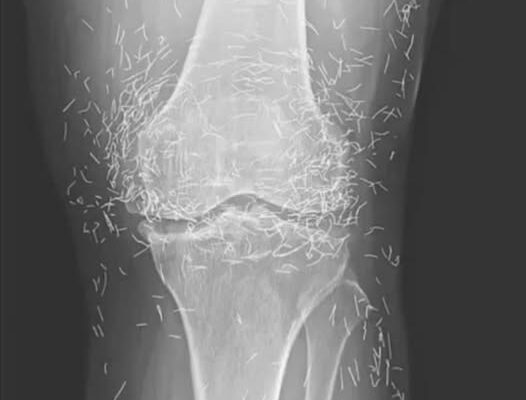

When a 65-year-old South Korean woman went in for knee pain, doctors weren’t expecting to strike gold. But that’s exactly what they found.

Acupuncture, a centuries-old alternative treatment, involves inserting needles into the body at specific points to relieve pain or treat illnesses. In this case, the needles— presumably made of gold — were intentionally left in her knees for continued stimulation.

He also warned that embedded needles can complicate X-ray readings. “The needles may obscure some of the anatomy,” Guermazi said in 2013.